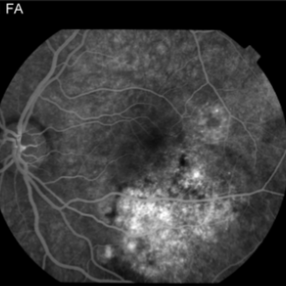

This 13 year old girl presented with mild painless progressive blurring of central vision left eye over the past several months. Visual Acuity was 20/25. She was noted to have a normal posterior segment on the right. In the affected left eye, retinal examination revealed a relatively flat, lightly pigmented lesion, with well-defined and scalloped edges. Clumps of associated pigment were noted. The OCT image shows subretinal fluid just inferior to the fovea. Choroidal osteoma can be associated with the development of subretinal neovascularization (particularly at the edges of the osteoma). Findings were suggestive of an early choroidal osteoma with some high echodensity on B scan ultrasound. Choroidal osteoma are usually unilateral, occur most often in females, and are diagnosed in the teen years.

Choroidal Osteoma Choroidal OsteomaNov 21 2014 by Thomas A. Ciulla, MD, MBA, FASRS This 13-year-old girl presented with mild painless progressive blurring of central vision left eye over the past several months. Visual acuity was 20/25. In the affected left eye, retinal examination revealed a relatively flat, lightly pigmented lesion, with well-defined and scalloped edges. Clumps of associated pigment were noted. This OCT image shows subretiinal fluid just inferior to the fovea. Choroidal osteoma can be associated with the development of subretinal neovascularization (particularly at the edges of the osteoma). Photographer: Thomas Steele Condition/keywords: choroidal neovascular membrane (CNVM), choroidal neovascularization (CNV), choroidal osteoma, macular choroidal osteoma